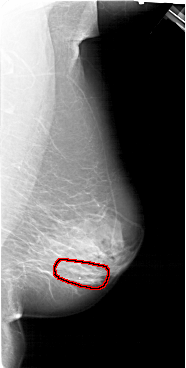

A_1390_1.LEFT_CC

RIGHT_MLO LINES 6616 PIXELS_PER_LINE 3331 BITS_PER_PIXEL 12 RESOLUTION 43.5 OVERLAY

FILE: A_1390_1.RIGHT_MLO.OVERLAY

TOTAL_ABNORMALITIES 1

ABNORMALITY 1

LESION_TYPE CALCIFICATION TYPE PLEOMORPHIC DISTRIBUTION LINEAR

ASSESSMENT 4

SUBTLETY 3

PATHOLOGY BENIGN

TOTAL_OUTLINES 1

BOUNDARY